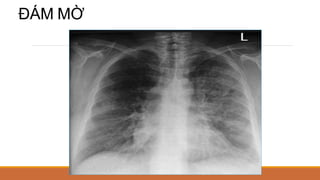

CÁC DẠNG TỔN THƯƠNG NHU MÔ PHỔI

ĐÁM MỜ

KHỐI MỜ (ĐK>3CM)

NỐT MỜ (ĐK</=3CM)